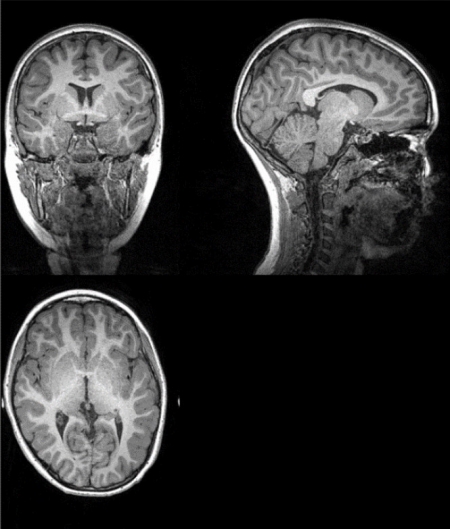

Analizan cómo el cerebro de personas obesas ven la comida de forma diferente al de quienes tienen un peso saludable

Perder menos peso tras una dieta en la adolescencia está relacionado con que las áreas cerebrales de la motivación por comer y del efecto recompensante de la comida mantengan una conexión mayor, según un trabajo publicado recientemente